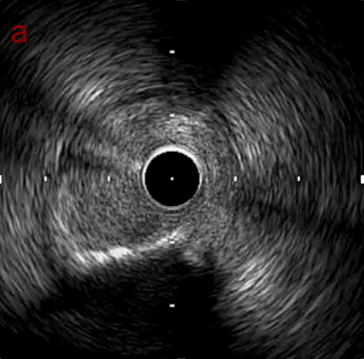

IVUS imaging

PreのIVUSではaの部位のみlipid plaqueを認め削ることでdistal embolismのリスクがあり、そのほかは270度の偏心性石灰化であるがwire biasは良好。

Pre